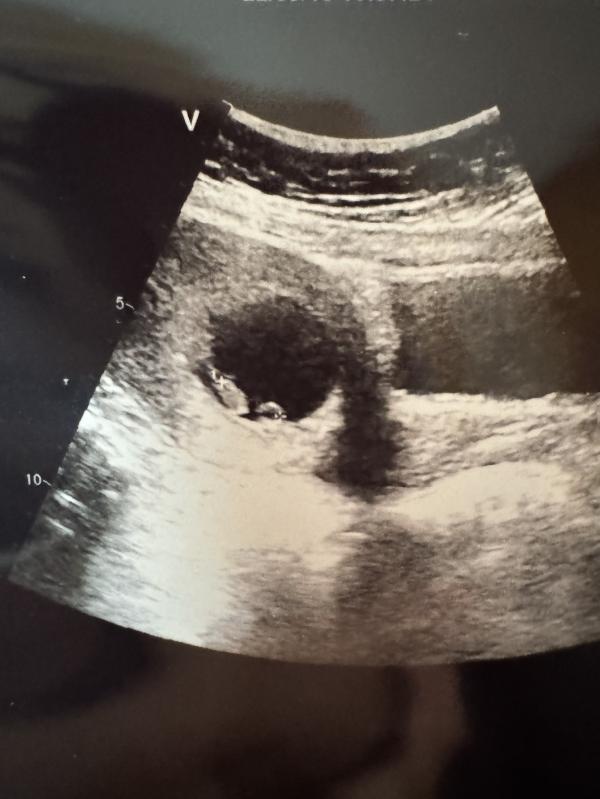

Вчера платно ходила на УЗИ увидела малыша😍☺️ по месячным срок соп тубэьэр, сердечко бьется 🤩

Коробун уонна 2 отдельных баар диибин, кружочек типо питанията бьлах да диэбиппин быраас тобото ди диэбитэ😂😂